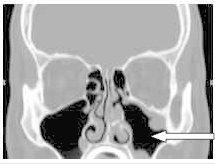

Na obrazie TK zaznaczono zatokę

Ilustracja do pytania 16

A. czołową w przekroju czołowym.

B. czołową w przekroju strzałkowym.

C. szczękową w przekroju strzałkowym.

D. szczękową w przekroju czołowym.